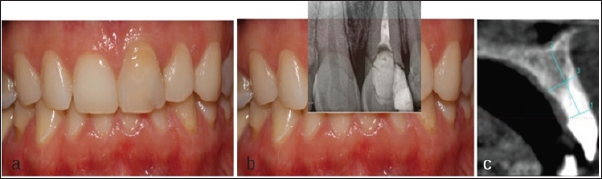

Patient of 28 years attended to the Department of Oral Implantology of the Universitat Internacional de Catalunya because of mobility in 2.1. After a head-trauma. After clinical and radiological examination through periapical X-ray and CBCT (Cone Beam Computered Tomography) scan non-restorable root fracture of tooth 2.1 was diagnosed (Figure 1). Due to the high aesthetic demands and the thin buccal plate, it was decided to perform the atraumatic extraction of the 2.1 and to performed a ridge preservation of the alveolus to place a single implant after the healing period. Atraumatic extraction of tooth 2.1 was carried out and the alveolus was preserved following the Ice-Cone technique described by Elian et al. [6], using a collagen membrane (Bio-guide®, Geistlich Biomaterials, Parma, USA) and Xenograft (Bio-Oss, Geistlich Biomaterials, Parma, USA), later on membrane exposure was covered with soft tissue graft obtained from the palate fixed with single sutures and finally provisionalized with Maryland bridge (Figure 2).

Figure 1: Initial Situation of 28-Year Old Woman, with High Smile Line and Non-Restorable Root Fracture of 2.1: (a) Frontal View; (b) Periapical Radiograph at Baseline; (c) Axial Slice of the Cone Beam Computered Tomography Scan.